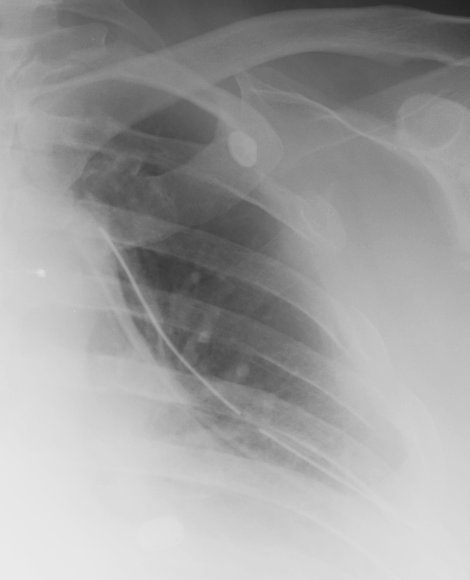

- Click on the image for a larger versionAAP chest radiograph. This demonstrates multiple left lateral rib fractures. The patient sustained a pneumothorax as well and a chest tube was placed.